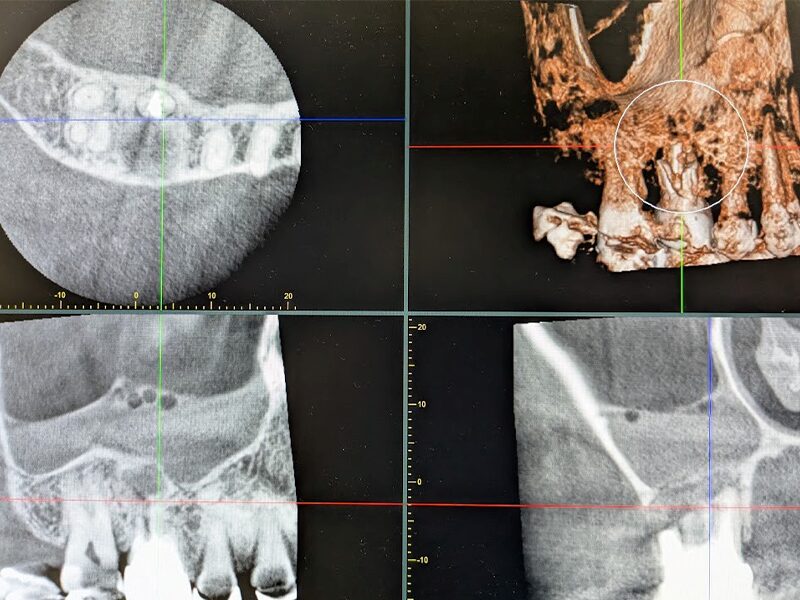

根管治療の再治療になりますが、歯根が弯曲・閉塞しているため根管治療で病巣が治癒せず、上顎洞粘膜の肥厚も残っております。

術後1年半の確認CTです。上顎洞粘膜の肥厚は消失。嚢胞摘出腔に骨が再生してきていることがわかります。再生がなかなか難しいと言われている皮質骨も再生してきております。